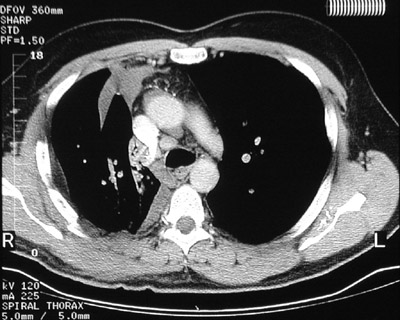

There is atelectasis involving the right upper lobe in this chest CT scan as a result of bronchial obstruction. The area of collapsed lung is dense mottled grey compared to the black adjacent aerated lung as seen in "bone window" setting.